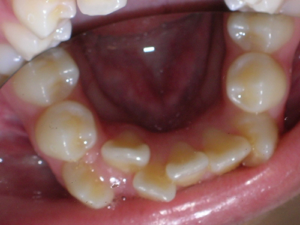

Here is what he looked like on the day that the braces were removed.

In the final photo, you can see the bonded retainer we used. A top nighttime removable retainer was made.